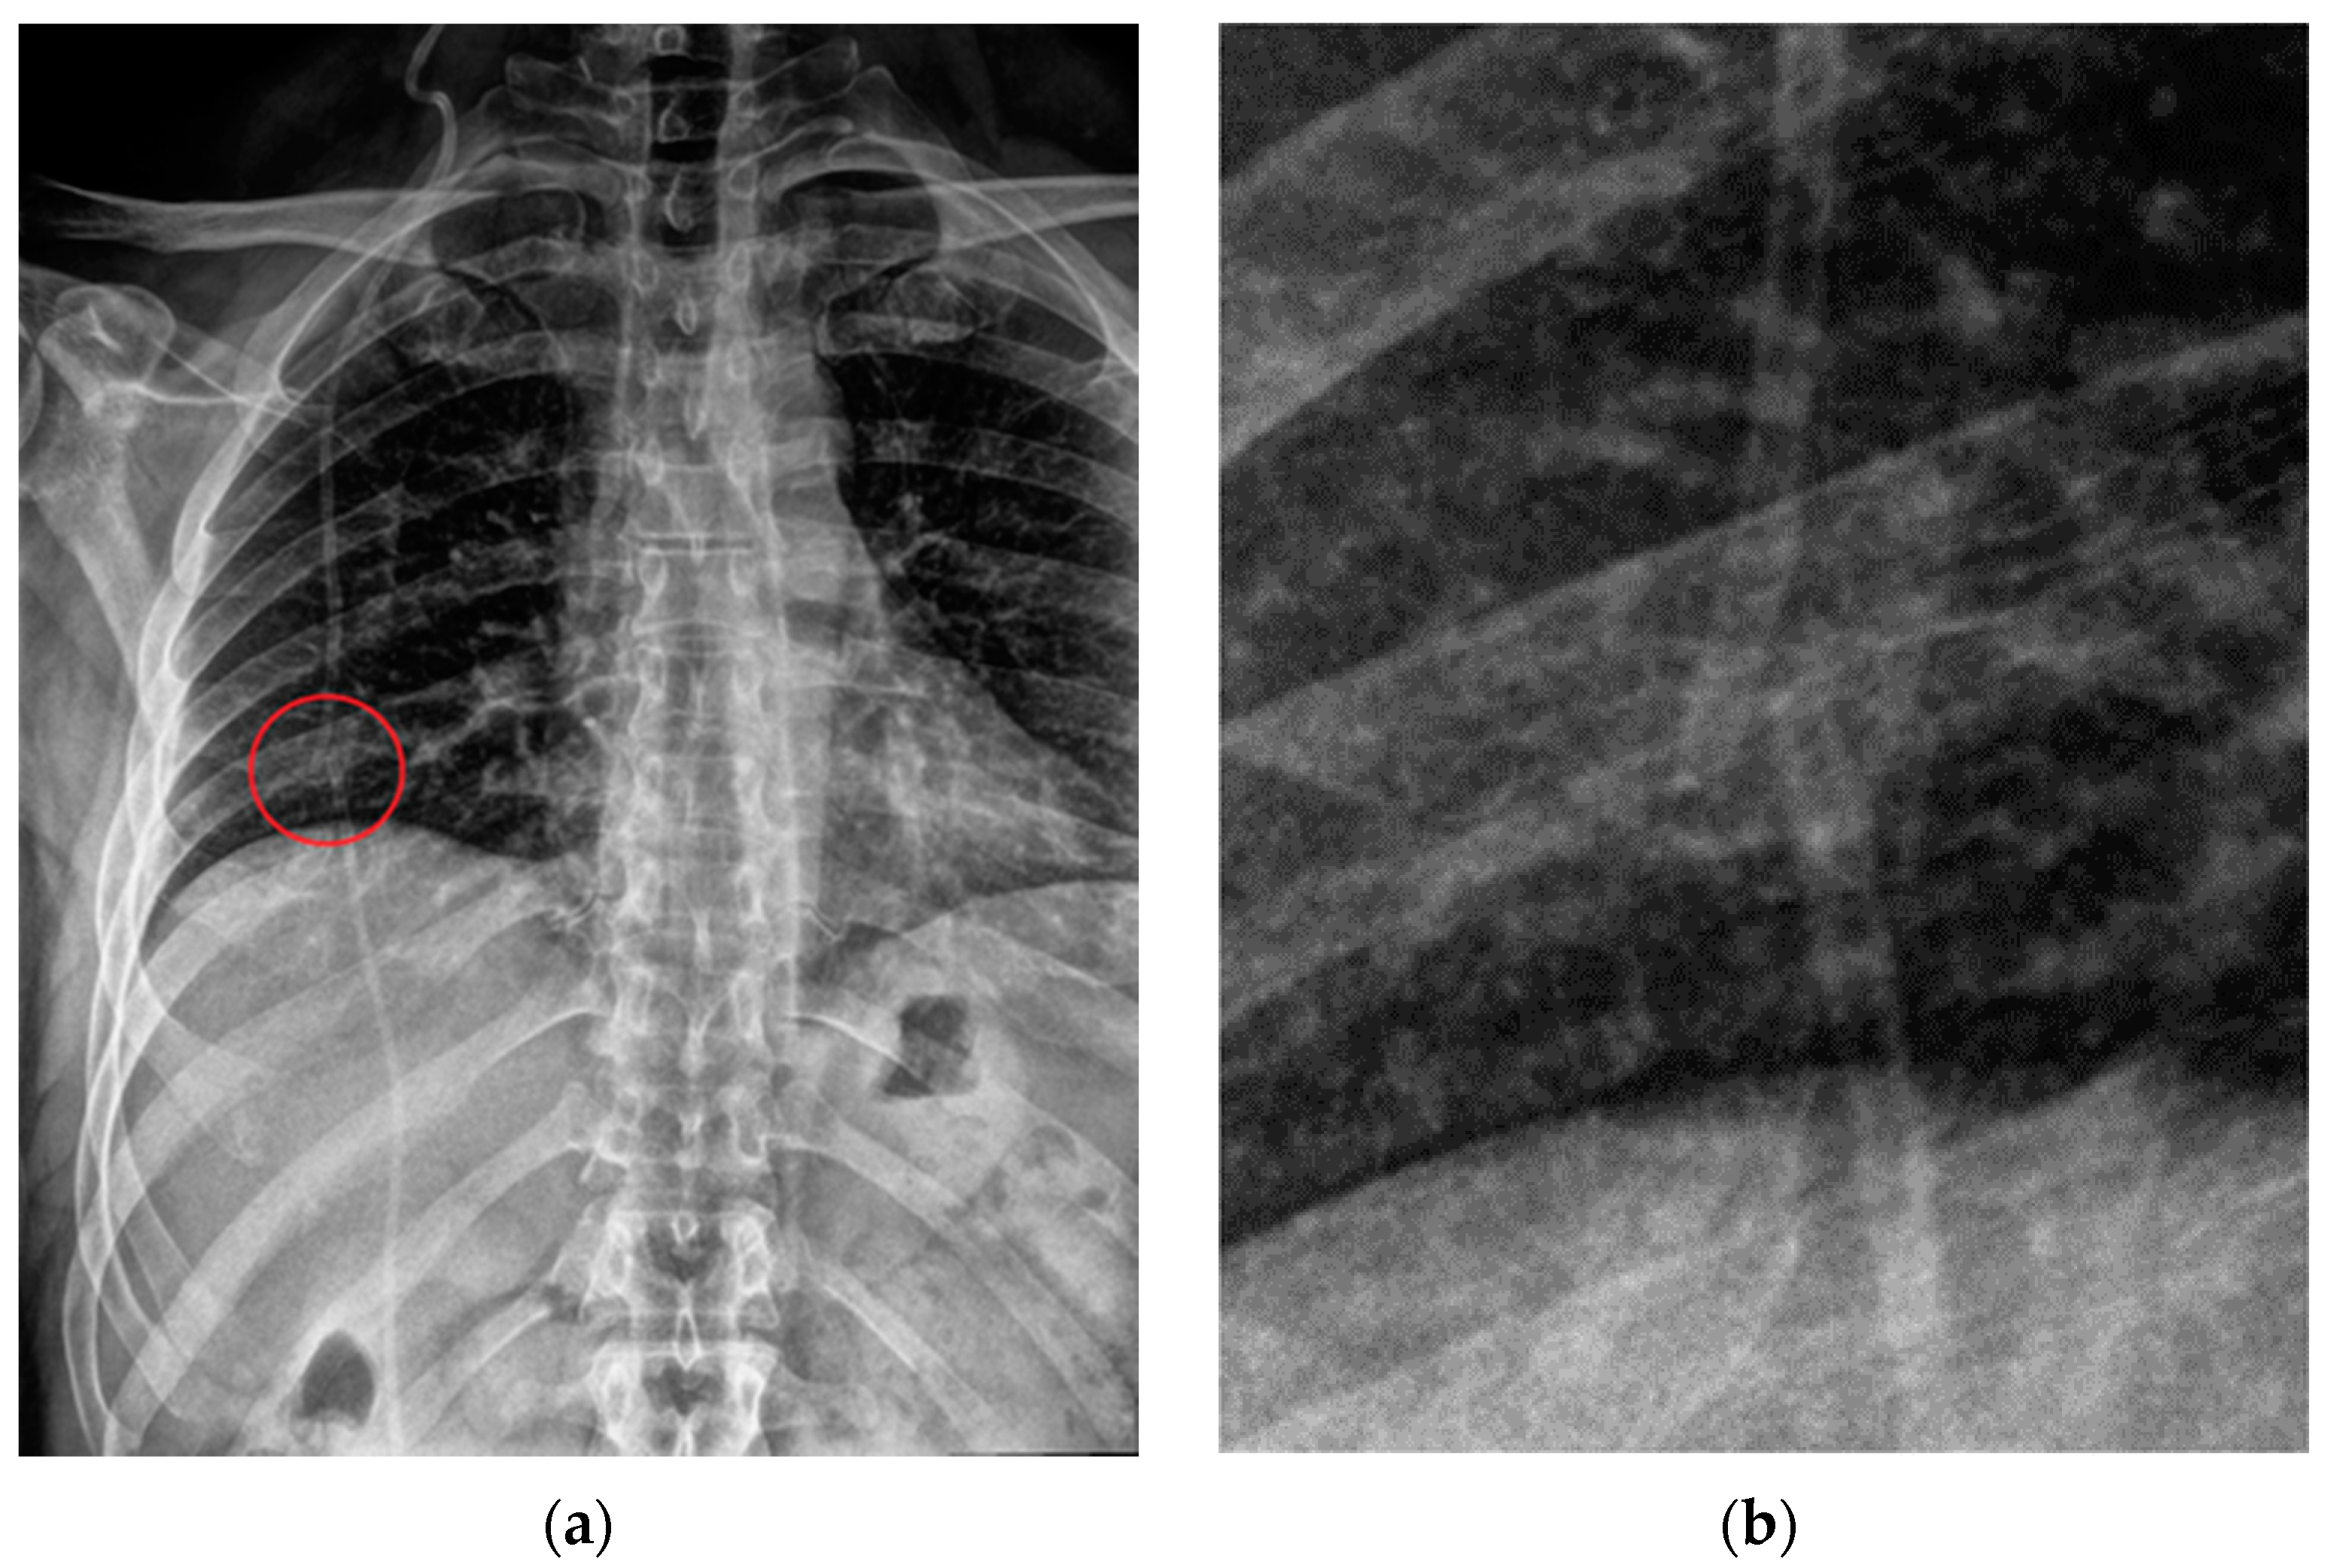

Complications that are visible on plain radiographs include breakages (Figure 33), disconnections and migrations of the distal catheter, pneumothorax, subcutaneous emphysema and, in VA shunts, features of pulmonary hypertension (Table 7) [3,47].

Figure 33.

Rupture of a VP shunt (red circle) visible on the PA view of a CXR (a), magnified in the second image (b).